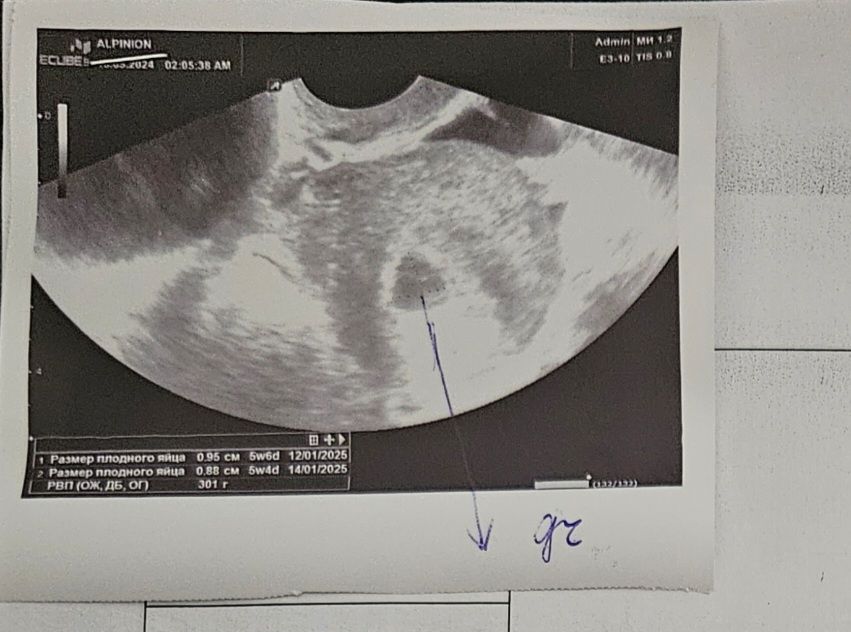

С хгч 5600 узи было такое

Через неделю уже было такое, но хгч больше не сдавала